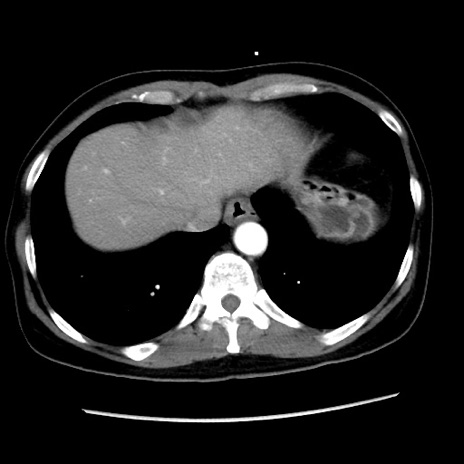

冠状断像

【症例】 50歳代女性

【主訴】 腹痛

【現病歴】前日生レバーを食べた。今朝に排便あり。 昼前に突然発症の腹痛を生じ、当院救急外来を受診した。

【既往歴】 子宮筋腫にてで子宮全摘後

【身体所見】 意識清明、腹部:平坦、軟、下腹部やや左を中心に圧痛・反跳痛あり、筋性防御あり

【データ】WBC 7800、CRP 0.07